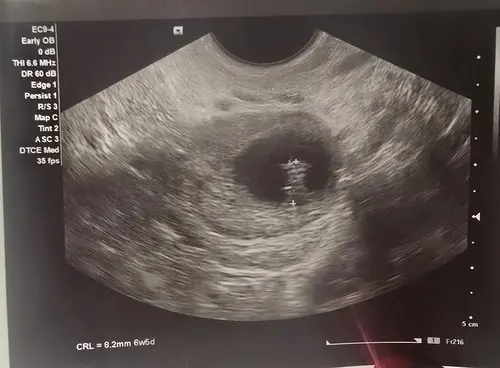

Ik kom net bij de verloskundige vandaan. Het gevoel zat zo goed. Ze kon geen hartslag vinden. Het hartje is vandaag gestopt met kloppen.

Hier ook gelukkig een gezond kindje al in ons midden, waar we mega dankbaar voor zijn. Maar sinds september vorig jaar weer een kinderwens. Toen gelijk zwanger, maar miskraam bij 5 weken. November weer zwanger, en zwangerschap op onbekende locatie. Bij 6 weken was er een vruchtzakje te zien op de echo en daarna toch een miskraam gekregen. Afgelopen mei weer zwanger en bij 10 weken een foute echo. Veel vocht rondom het hoofd en ruggetje, hydrops waarvoor doorverwijzing naar specialistisch ziekenhuis bij 11 weken. Syndroom van Turner geconstateer waarna met 12 weken we weer een miskraam hebben gehad.

Sterkte! Ik heb ook met 5 weken een miskraam gehad. Erg verdrietig. Wel was ik direct daarna zwanger zonder menstruatie tussendoor. Nu 7 weken zwanger en weet dat ik nog niet mag juichen. Maar een beetje positiviteit mag toch wel. Echo goed, kloppend hartje. Sterkte met het verlies!!! Je bent niet alleen en inderdaad hou vol. Het kan zo weer raak zijn. ❤️

Jeetje lieve meiden, wat komt het toch vaak voor.. Wij hebben al een zoontje van 3,5 jaar rondlopen. Afgelopen maandag echo gehad en helaas geen kloppend hartje meer met 7+3. Wat een teleurstelling en verdriet was dat.. Vandaag medicatie genomen en ben als het goed is alles “kwijt”. Fijn om te lezen dat het bij veel ook weer gelukt is. Geeft me hoop! Maar blijft denk ik toch altijd heel spannend en onzeker..